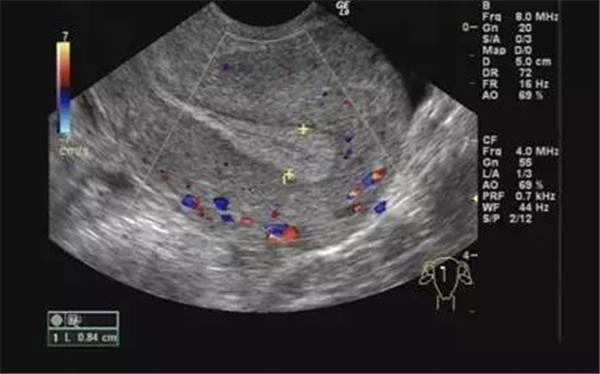

聲像圖特點:1、子宮增大邊界不規則。2、肌瘤結節呈低回聲、等回聲或強回聲。等回聲周邊可有低回聲暈呈假包膜。3、子宮內膜移位或變形。4、膀胱變形,易引起尿貯留。5、肌瘤結節周圍呈環狀及半環狀血流。阻力指數0.6±0.1。

聲像圖特征:1、子宮均勻性增大,邊界規則。2、子宮內膜線前移。3、子宮內回聲不均勻,低回聲、強回聲區,無包膜。4、子宮大小、內部回聲月經前后常有變化。5、腫塊周圍無環狀或半環狀血流,阻力指數約0.6。